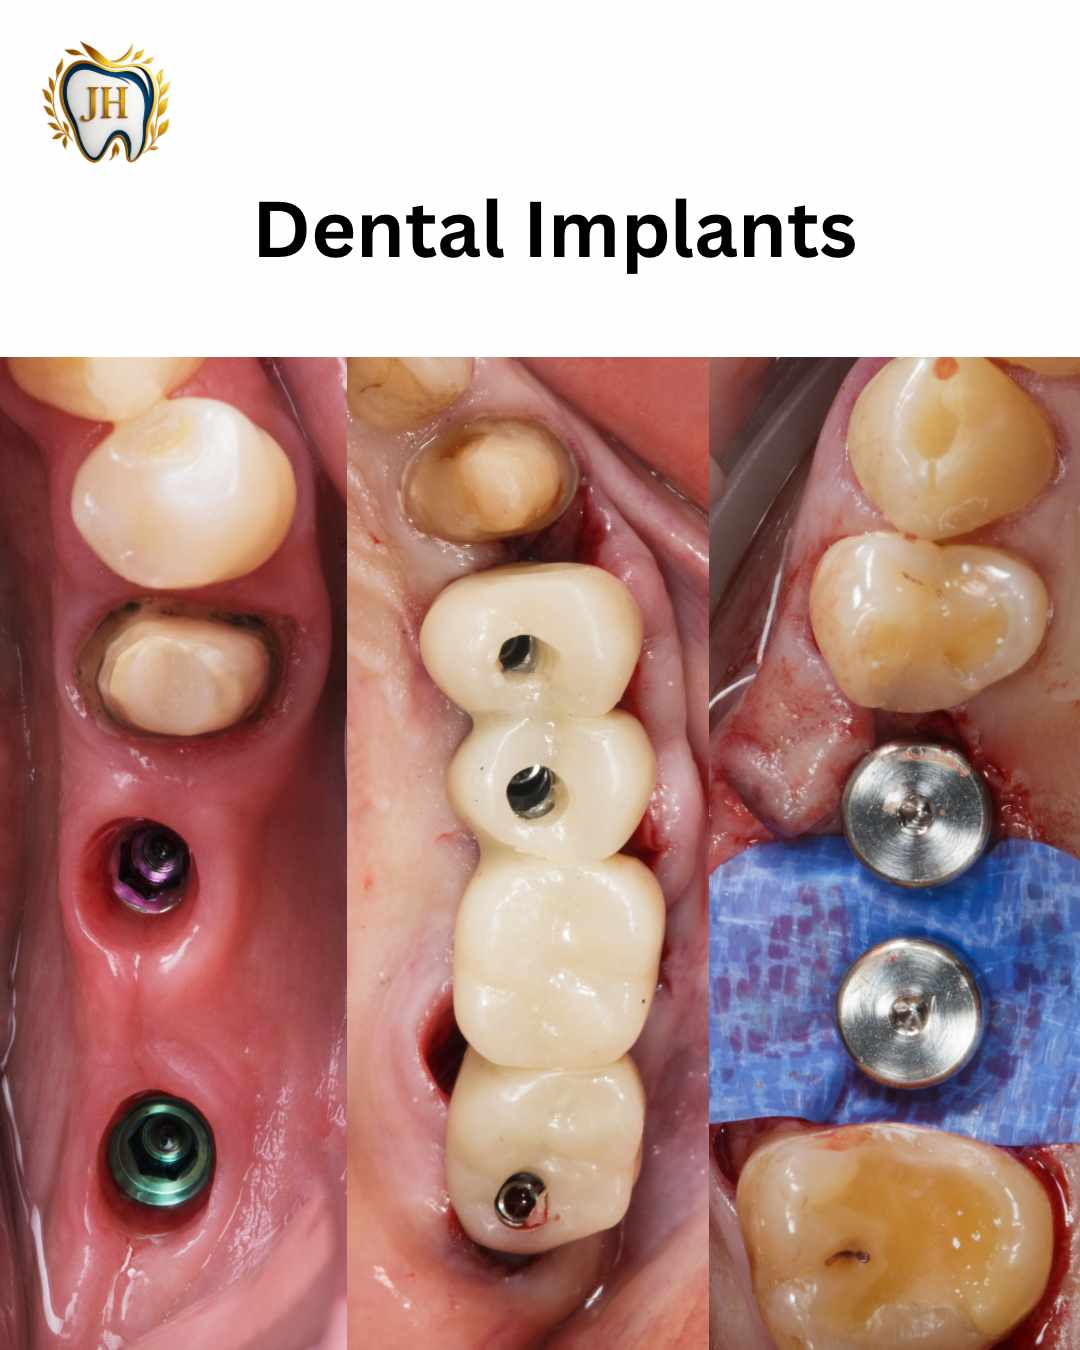

- Dental Implants